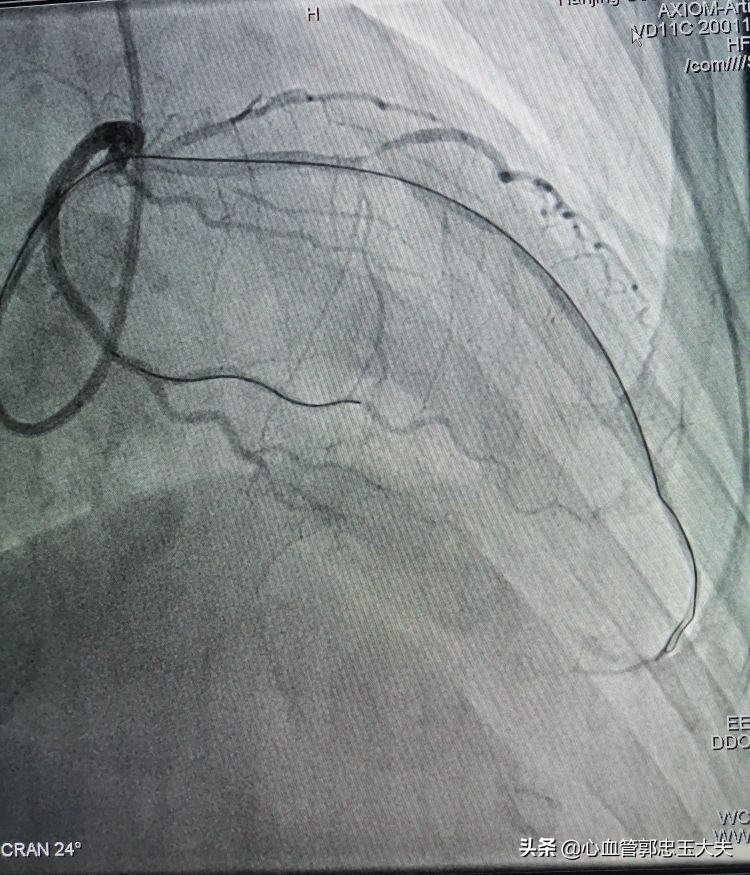

改变策略先在回旋支近段到远端植入支架2枚(如下图)

支架植入后,在回旋支再次预埋球囊,扩张后支撑力明显加强,微球囊通过闭塞病变,扩开闭塞血管。最后前降支植入支架,影像效果满意(如下图)

总结:该患者前降支中远段完全闭塞合并钙化,因此导丝通过病变非常困难,微球囊支撑后导丝过血管闭塞段,在回旋支预埋球囊扩张加强支撑,微球囊仍然难以通过闭塞病变。改变策略在回旋支植入支架后再次预埋球囊,支撑力明显加强,微球囊通过闭塞病变,扩张开病变血管,支架得以植入。